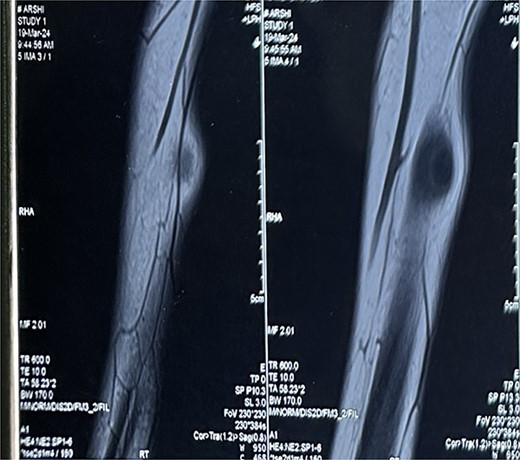

A 16-year-old female student who adheres to a vegetarian diet and has no known comorbidities presented to the Plastic Surgery outpatient department with a 2-month history of pain and swelling in the right forearm. There was no history of headache, seizure, or blurred vision. Despite the administration of over-the-counter analgesics, she did not experience any relief. In the proximal third of the right forearm, she was found to have swelling measuring 3 × 3 cm during the examination. It was non-tender, immobile, and attached to the underlying muscle, with a firm to rigid consistency. She was referred to the radiologist for a soft tissue ultrasound, which revealed a 14.6 × 4 mm hypoechoic lesion in the flexor aspect of the proximal right forearm. The lesion was accompanied by moving linear internal echoes, which are indicative of worm infestation/cysticercosis. The soft tissue MRI was indicative of a well-defined cystic lesion with an eccentric mural nodule in the intramuscular plane, as well as mild perilesional oedema (Fig. 1). The patient received oral Albendazole at a dose of 400 mg twice daily combined with nonsteroidal anti-inflammatory medications for 6 weeks; however, the swelling did not improve with this treatment. She was subsequently admitted and planned for surgical excision. Biochemical tests yielded normal results, and after obtaining informed consent, she proceeded to surgery. The cyst was discovered intraoperatively, embedded between the muscle fibres (Fig. 2). It was excised on the table, revealing scolex (Fig. 3), and the cut specimen was subsequently sent for histopathological examination which confirmed the diagnosis (Fig. 4). Albendazole was also recommended to the patient’s family members in order to prevent recurrence and eliminate the carrier state. At the 2-month follow-up, the patient is asymptomatic and conducting all of her activities in the same manner as before.

MRI Soft tissue of right forearm: suggestive of well-defined cystic lesion with eccentric mural nodule in intramuscular plane with mild perilesional oedema.